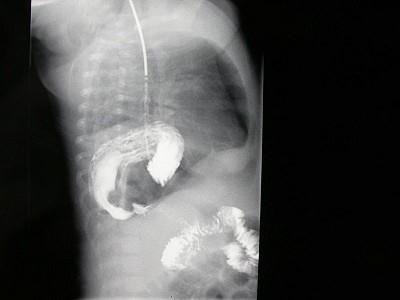

女,1岁,反复呕吐伴中度营养不良,结合影像,最可能的诊断为?(?)A.肺脓疡B.膈疝C.食道裂孔疝D.包裹性液气胸E.胃扭转

问题 女,1岁,反复呕吐伴中度营养不良,结合影像,最可能的诊断为?(?)

选项 A.肺脓疡 B.膈疝 C.食道裂孔疝 D.包裹性液气胸 E.胃扭转

答案 C